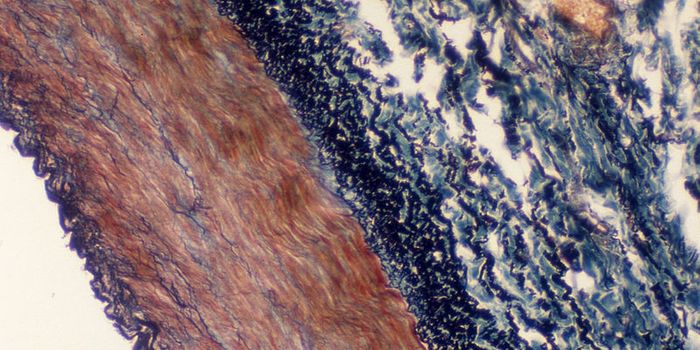

FEB 09, 2024CancerHistopathology describes the process of examining pieces of tissue using a microscope. Light microscopic (LM) exam ...